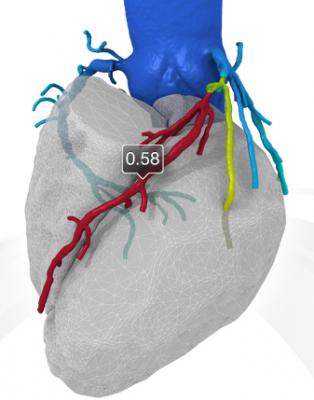

Heartflow's FFR-CT showing coronary blood flow being impacted by a blockage. The system offers a virtual FFR number that has good correlation with invasive, catheter-based FFR.

Photo 2, showing HeartFlow's CT-FFR report for the same vessel segment as shown in Photo 1.

The clearance may open a new era of coronary CT imaging, where a single scan can show blood flow with specific FFR flow rates for all segments in the heart. This may eliminate the need to perform diagnostic catheter angiography or to perform invasive catheter-based FFR tests. FFR-CT shows the exact area of blockages, the impact each has on flow and can help guide treatment and aid in interventional procedural navigation. Coronary CT experts predict the technology also may eliminate the need for myocardial perfusion nuclear imaging and other tests usually performed on patients presenting to emergency departments with chest pain.

The HeartFlow FFR-CT software can non-invasively provide an estimate of FFR using data from a CT scan of the patient’s heart. Doctors can use the estimate, along with other clinical patient data, to determine the likelihood that the actual FFR is below accepted limits and whether or not a more accurate FFR assessment using cardiac catheterization is necessary. It is expected the technology will greatly reduce the number of patients who are currently sent to the cath lab only to find their blood flow through a partial blockage is normal.

The Heart Flow FFR-CT software is housed at HeartFlow Inc.’s headquarters in Redwood City, Calif. A healthcare professional electronically sends the patient’s CT scan data to HeartFlow where a case analyst creates 3-D computer models of different sections of the patient’s heart and runs a blood flow simulator program on the models. After analyzing the data and the models, the case analyst electronically sends a report with the estimated FFR-CT values displayed as color images of the patient’s heart.